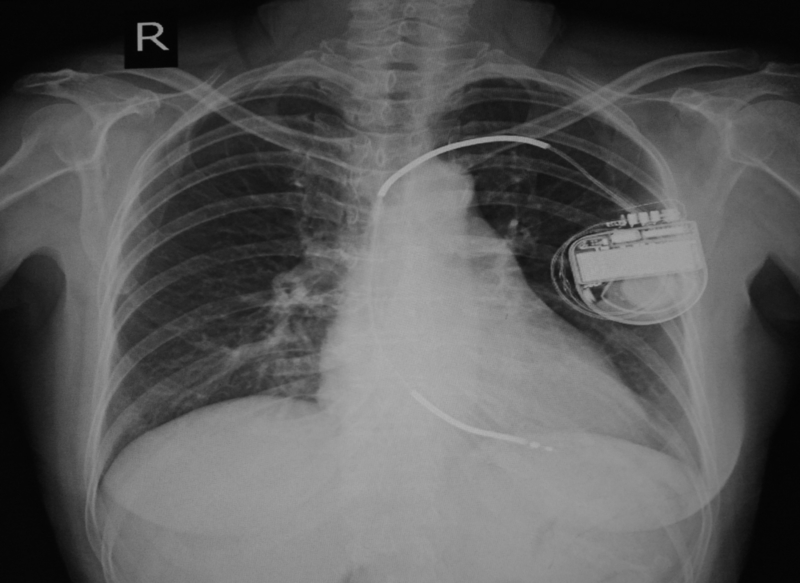

Implantable cardioverter-defibrillator (ICD) use is associated with reduced short- and long-term mortality in patients with heart failure, according to late breaking research presented in a Hot Line Session at ESC Congress 2019 together with the World Congress of Cardiology and published in Circulation.

Patients with heart failure are at increased risk of potentially lethal ventricular arrhythmias (heart rhythm disorders) and sudden cardiac death. ICDs are used to correct these arrhythmias and prevent sudden death.

ESC guidelines recommend an ICD for primary prevention in symptomatic patients with heart failure with reduced ejection fraction (HFrEF), provided they are expected to survive substantially longer than one year with good functional status. It is called primary prevention because patients have not had a ventricular arrhythmia before.